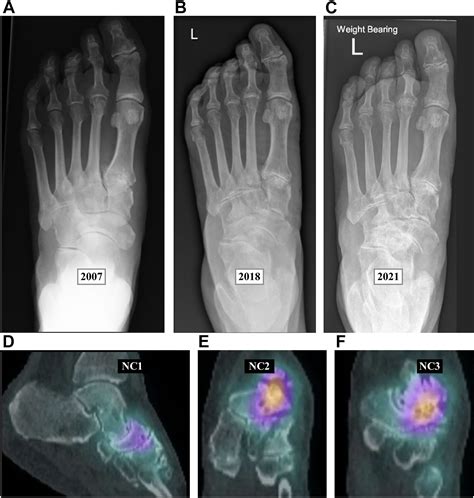

Mueller Weiss Syndrome is a rare degenerative disease of the navicular bone, a small, boat-shaped bone located in the midfoot. Unlike fractures caused by acute trauma, this syndrome occurs when the bone loses its blood supply, leading to fragmentation and collapse. While the exact cause remains somewhat elusive, it is frequently associated with mechanical stress, congenital anomalies, or systemic conditions that impede vascular flow.

Diagnosing Mueller Weiss Syndrome requires a comprehensive evaluation by a foot and ankle specialist. Because the symptoms can mimic other conditions like tarsal coalition or arthritis, imaging is essential for a precise diagnosis.

X-ray (Weight-bearing) The primary tool to visualize the navicular bone's fragmentation and collapse.

MRI Highly sensitive; used to detect early signs of edema and bone marrow changes.

CT Scan Best for detailed assessment of bone morphology and planning potential surgical intervention.

• mueller weiss syndrome radiology

• mueller weiss disease radiology

• mueller weiss syndrome xray